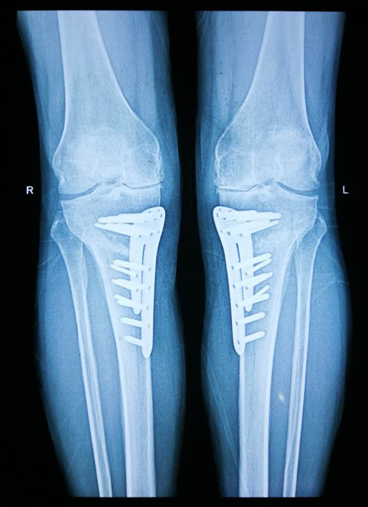

病 例

王XX,女,62岁,双膝关节疼痛,尤其左膝内侧疼痛难耐

此类手术后功能恢复良好,膝关节评分较术前明显提高,患者对术后疗效满意

胫骨高位截骨术

通过经过高位截骨,矫正力线,适用于合并严重内翻的膝关节骨性关节炎,可延缓关节炎进展,保留了膝关节的正常活动功能—称之为保膝治疗.随着技术水平的提高,内固定材料的稳定性增强,此术式用于早中期的膝关节关节炎的治疗,延缓内侧关节的破坏,延长膝关节的使用寿命,推后或避免膝关节的置换,进而缓解疼痛,提高患者生活质量。